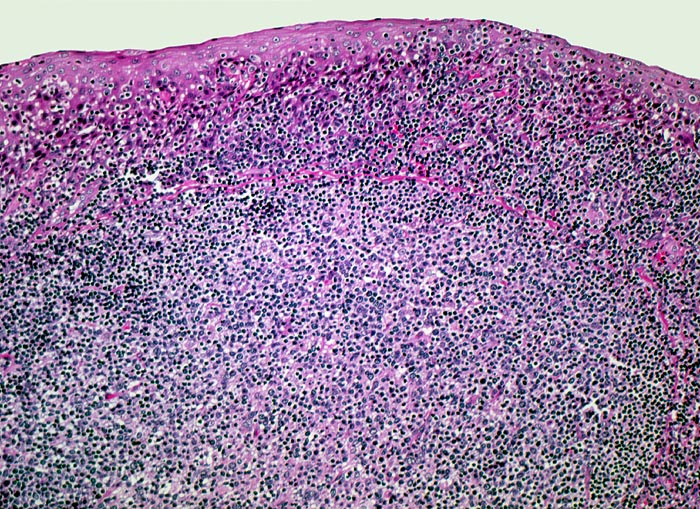

Tonsille mit Sekundärfollikel

Ein sekundärer Lymphfollikel mit Keimzentrum wird bedeckt von Plattenepithel der Mundschleimhaut. Zahlreiche Lymphozyten infiltrieren das darüberliegende Epithel, was in der Tonsille ein Normalbefund darstellt.